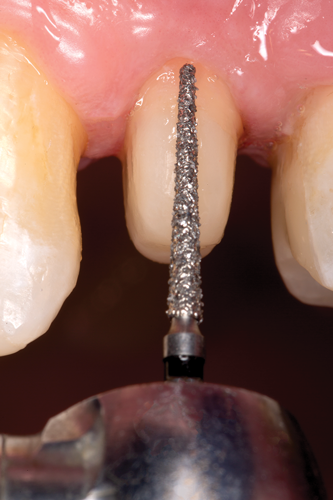

After polymerization and removal of the stopper, the fiber post was cut with a diamond bur to the predetermined length (Figure 17). It should be noted that the clinician should never use a serrated instrument or shears to cut the post to avoid damaging the integrity of the post. The remaining sound tooth structure (ferrule) was etched for 15 seconds with a 37.5% phosphoric acid semigel, rinsed for 5 seconds, and air-dried (Figure 18). With the use of a sable brush, silane was then applied to the coronal portion of the fiber post and existing composite material and air-dried. A universal adhesive was applied to the tooth structure, existing composite material, and fiber post and allowed to dwell for 10 seconds, then air-dried and light-cured (Figure 19).

Fig 17. After polymerization and removal of stopper, the fiber post was cut with a diamond bur to the predetermined length.

Figure 17